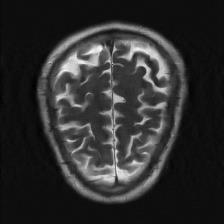

Recently, deep neural networks have greatly advanced undersampled Magnetic Resonance Image (MRI) reconstruction, wherein most studies follow the one-anatomy-one-network fashion, i.e., each expert network is trained and evaluated for a specific anatomy. Apart from inefficiency in training multiple independent models, such convention ignores the shared de-aliasing knowledge across various anatomies which can benefit each other. To explore the shared knowledge, one naive way is to combine all the data from various anatomies to train an all-round network. Unfortunately, despite the existence of the shared de-aliasing knowledge, we reveal that the exclusive knowledge across different anatomies can deteriorate specific reconstruction targets, yielding overall performance degradation. Observing this, in this study, we present a novel deep MRI reconstruction framework with both anatomy-shared and anatomy-specific parameterized learners, aiming to "seek common ground while reserving differences" across different anatomies.Particularly, the primary anatomy-shared learners are exposed to different anatomies to model flourishing shared knowledge, while the efficient anatomy-specific learners are trained with their target anatomy for exclusive knowledge. Four different implementations of anatomy-specific learners are presented and explored on the top of our framework in two MRI reconstruction networks. Comprehensive experiments on brain, knee and cardiac MRI datasets demonstrate that three of these learners are able to enhance reconstruction performance via multiple anatomy collaborative learning.